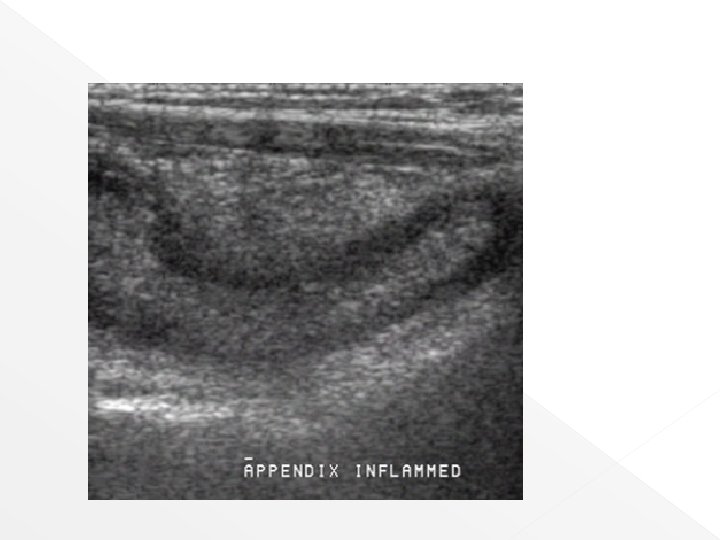

Acute appendicitis Abdominal x-ray (AXR) US › Non-specific finding › Approximately 10% a calcified appendicolith › Generally, the normal cannot be defined with US, clear visualization of the appendix is suggestif of inflammation › Swollen, non compressible appendix greater than 7 mm in diameter with a target or bulls-eye configuration is produced by the hypoechoic dilated appendiceal lumen › Assymetrical wall thickening due to phlegmonous infiltration, an appendicolith with acoustic shadowing

US finding › Echogenic hallo form by omental tissues draped over the appendix › Free fluid in the culdesac › Atony in the terminal ileum with compression US